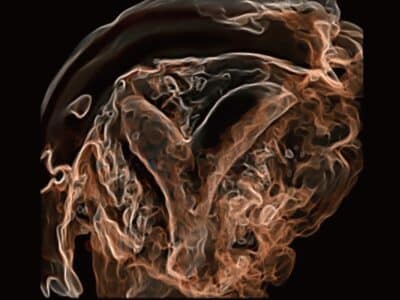

S-Live Silhouette

Díky použití virtuálního světelného zdroje a efektu stínování vidí S-Live Silhouette skrz povrch a jasně vykresluje obrysy kostí, orgánů, dutin, cévních stěn a dalších vnitřních struktur.

Nástroj pro identifikaci normální anatomie a diagnostiku komplexních vrozených vad.